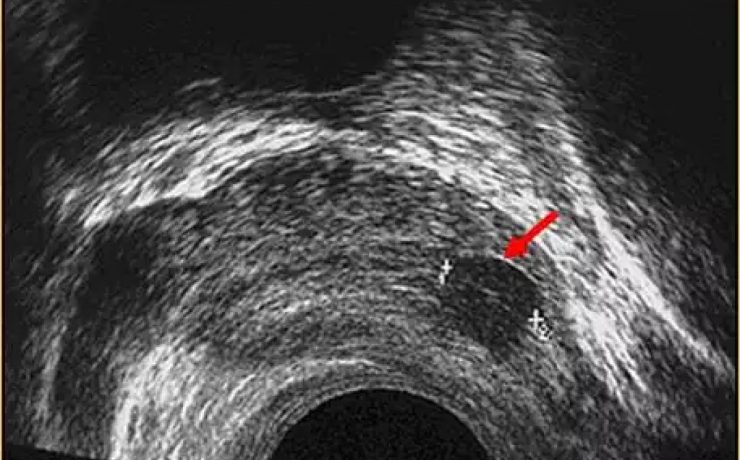

En este estudio se analiza la utilidad del ultrasonido en el estudio de la paciente estéril, específicamente con ultrasonido con aplicación de doppler, de Power doppler y la ecografía 3D para analizar los cambios cualitativos y cuantitativos que se observan en la irrigación del ovario en pacientes estériles, en pacientes